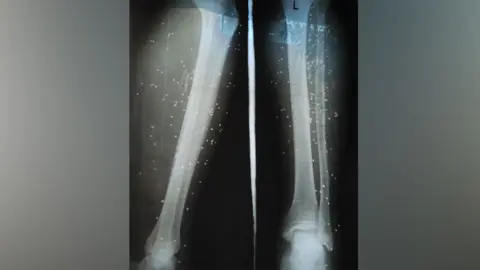

In India, snakebites have emerged as a pressing health crisis, claiming approximately 50,000 lives each year—almost half of the global total. Survivors, like Devendra, a farmer who suffered a snakebite while picking mulberry leaves, often recount the harrowing effects of delayed treatment. Devendra was hospitalized four days after his bite due to severe pain, resulting in a leg amputation. His case underscores the urgent need for timely medical intervention.